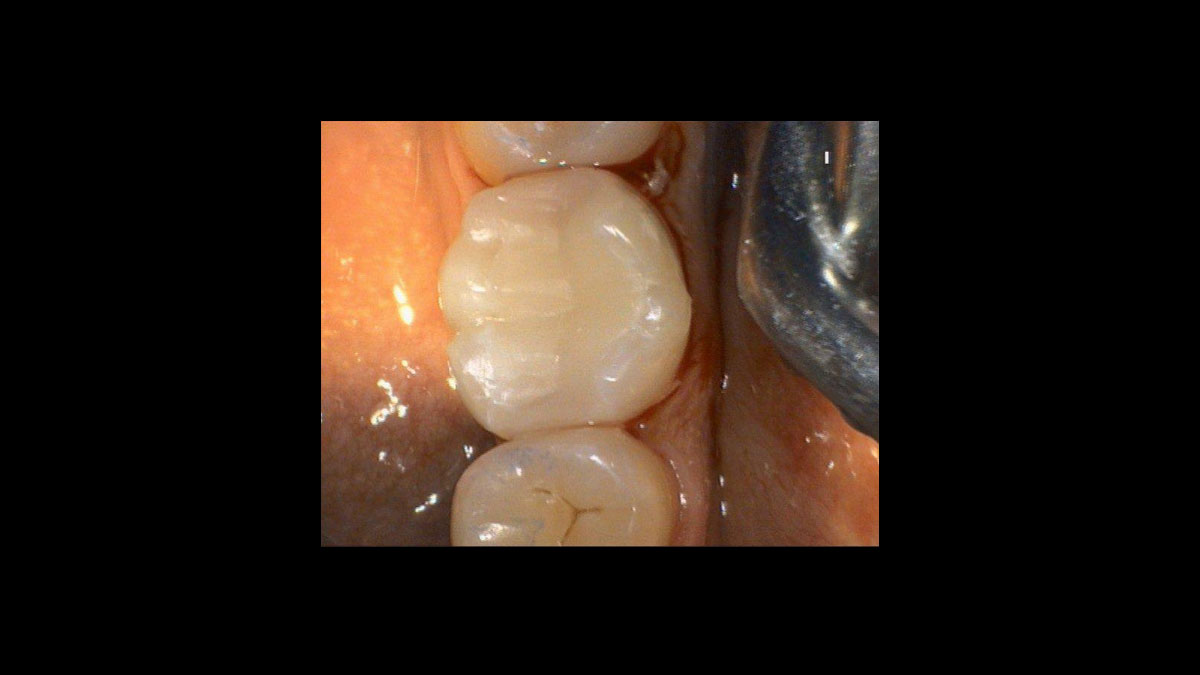

Cirugía

• Cirugía

• Preparación del tejido gingival antes de la toma de impresiones dentales

Preparación del tejido gingival antes de la toma de impresiones dentales